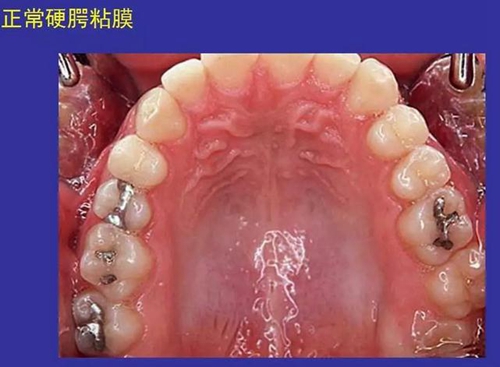

①口腔黏膜(oral mucosa):口腔內(nèi)的濕潤(rùn)襯里

一、口腔黏膜感染性疾病圖示